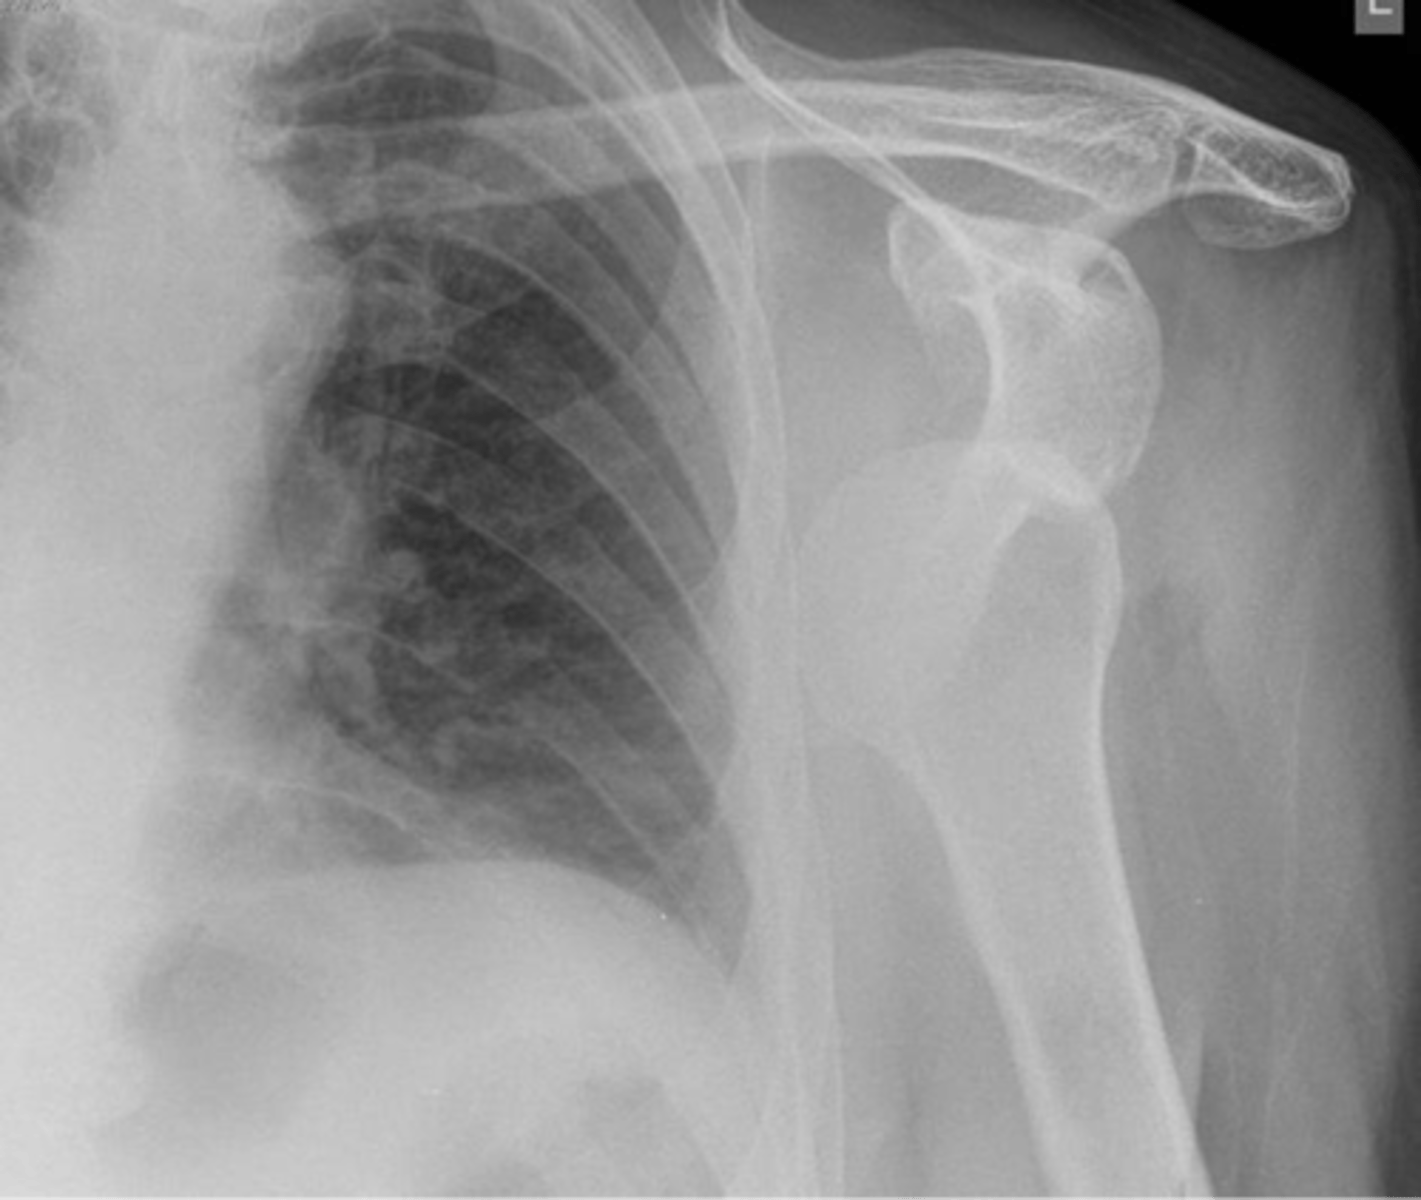

Condition: anterior GHJ dislocation

REALLY important to know BEFORE you relocate the humerus into the GHJ to know where the fracture(s) is and the integrity of the neurovascular structures

What is this image depicting? In an ideal scenario, determining this diagnosis is important before what? Why?